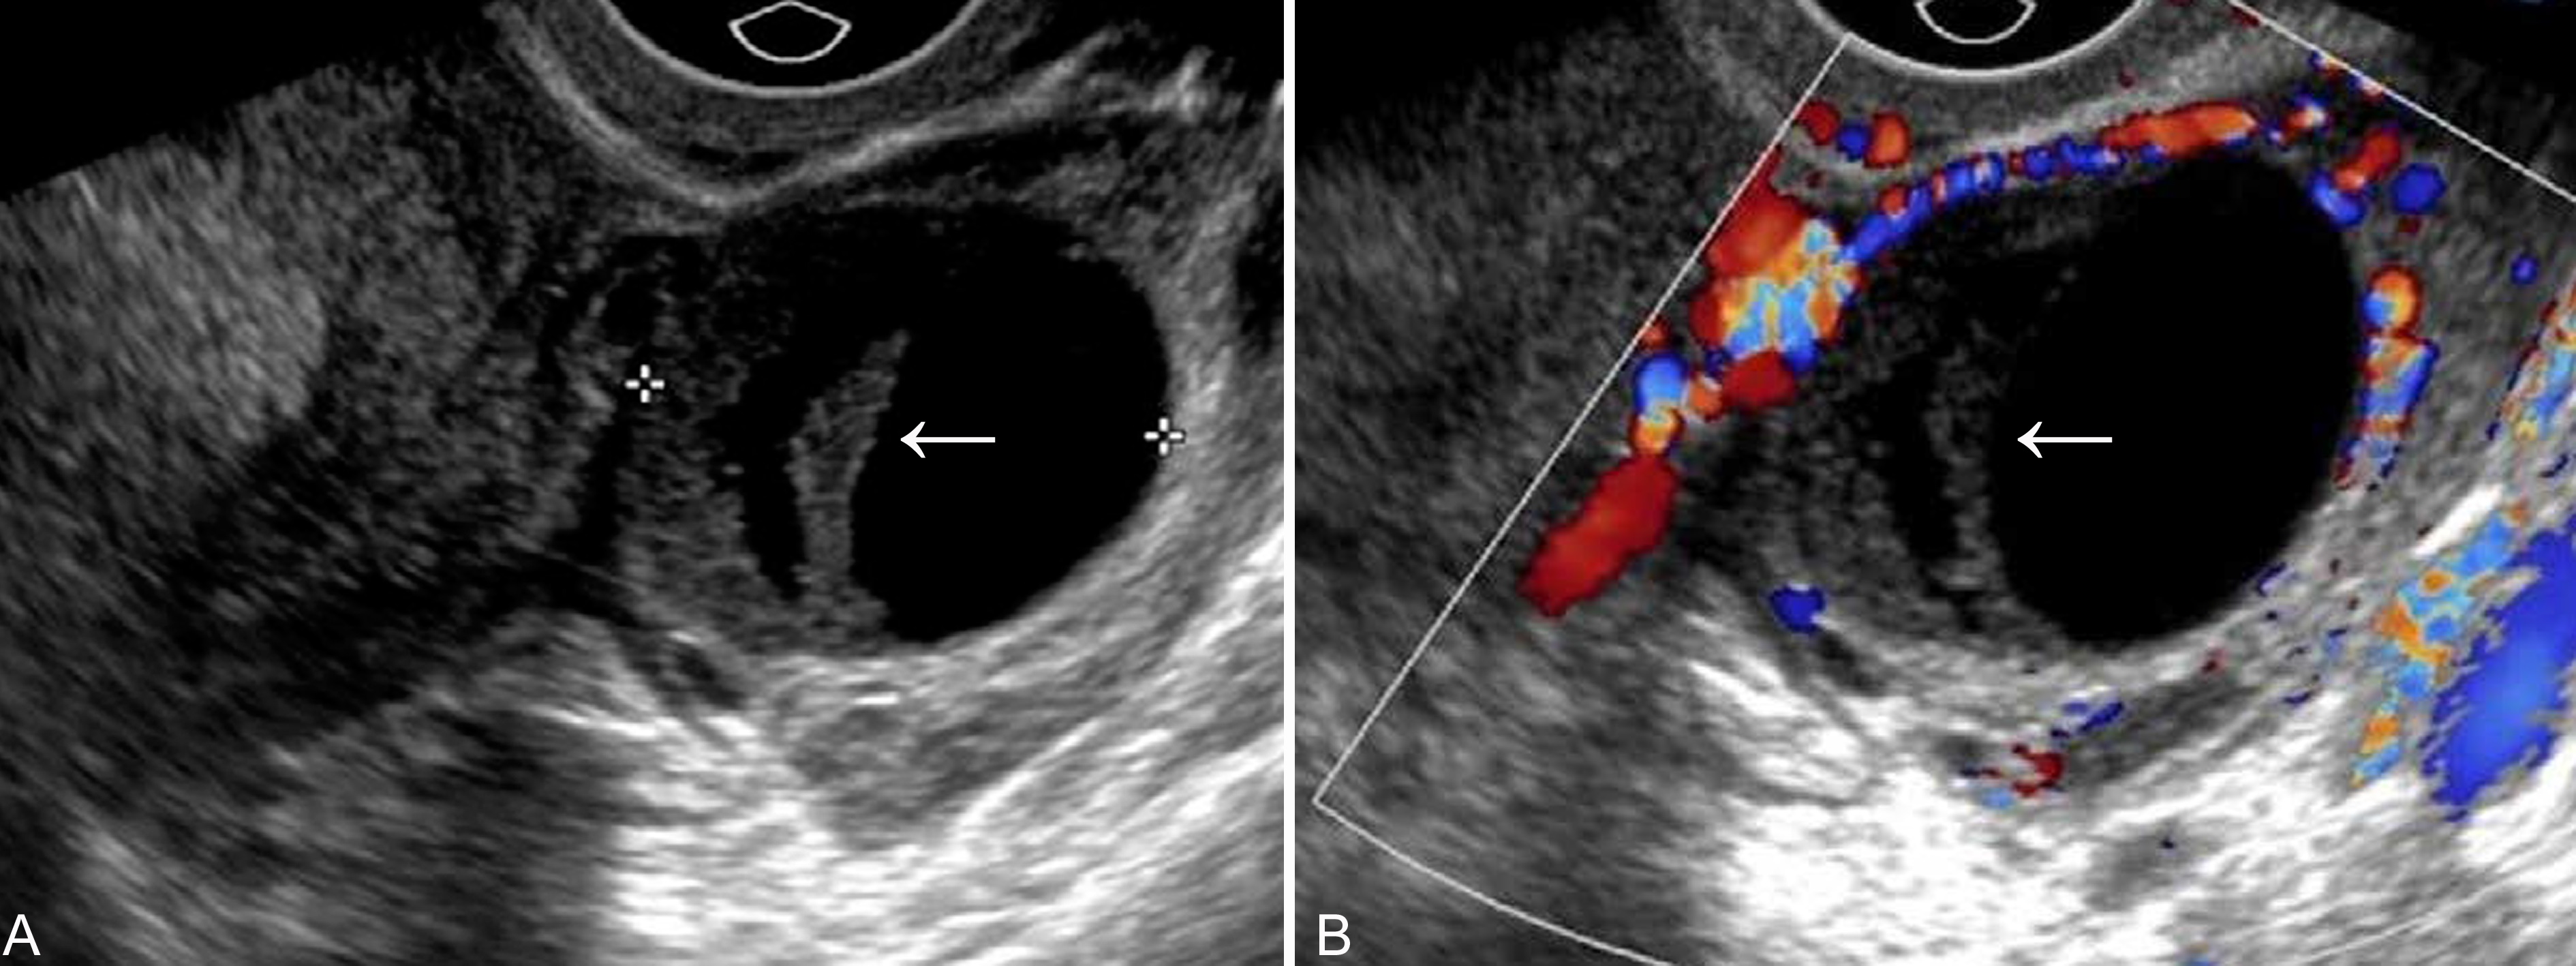

黄体囊肿(corpus luteum cyst)是妊娠期最常见的卵巢瘤样病变,可占卵巢局限性病变的14.2%。受精卵植入24小时以后,滋养层细胞分泌的绒毛膜促性腺激素刺激黄体形成妊娠黄体(corpus luteum of pregnancy)。在妊娠前10周内,妊娠黄体是孕妇体内孕激素和雌激素的主要产生部位,对促进子宫内膜蜕膜化和维持妊娠的正常进行有重要作用。此后,妊娠黄体的功能逐渐由胎盘代替,几乎均在妊娠第16周~18周以后消退。典型的妊娠黄体超声显像检查显示为附件区的无回声区,直径2cm~3cm,壁显示稍厚,内部为单房性,并可合并有少量点状低回声,此种回声多数无病理意义,几乎均在产前检查中偶然发现。如果妊娠黄体不消退,或持续增大,内部囊腔扩大,可形成黄体囊肿。超声显像检查显示囊肿直径多在4cm~6cm之间,形态规则,边缘清晰,壁较厚,但均匀一致(图1);内部多显示为无回声区,有时可见纤细的分隔回声;如果合并囊内出血,可以在囊腔无回声区内显示较粗的点状低回声,分布均匀或不均匀(图2A),CDFI检查周围血流稍增多或显示环状血流(图2B)。多数黄体囊肿较小,个别情况下囊肿可相当大,偶尔可以超过10cm;部分囊肿可以不消退,甚者维持到妊娠晚期,直至分娩。

图26-6黄体囊肿出血声像图:A:囊肿内显示不甚均匀的低回声,下方显示无回声;B:囊肿内显示不均匀型低回声